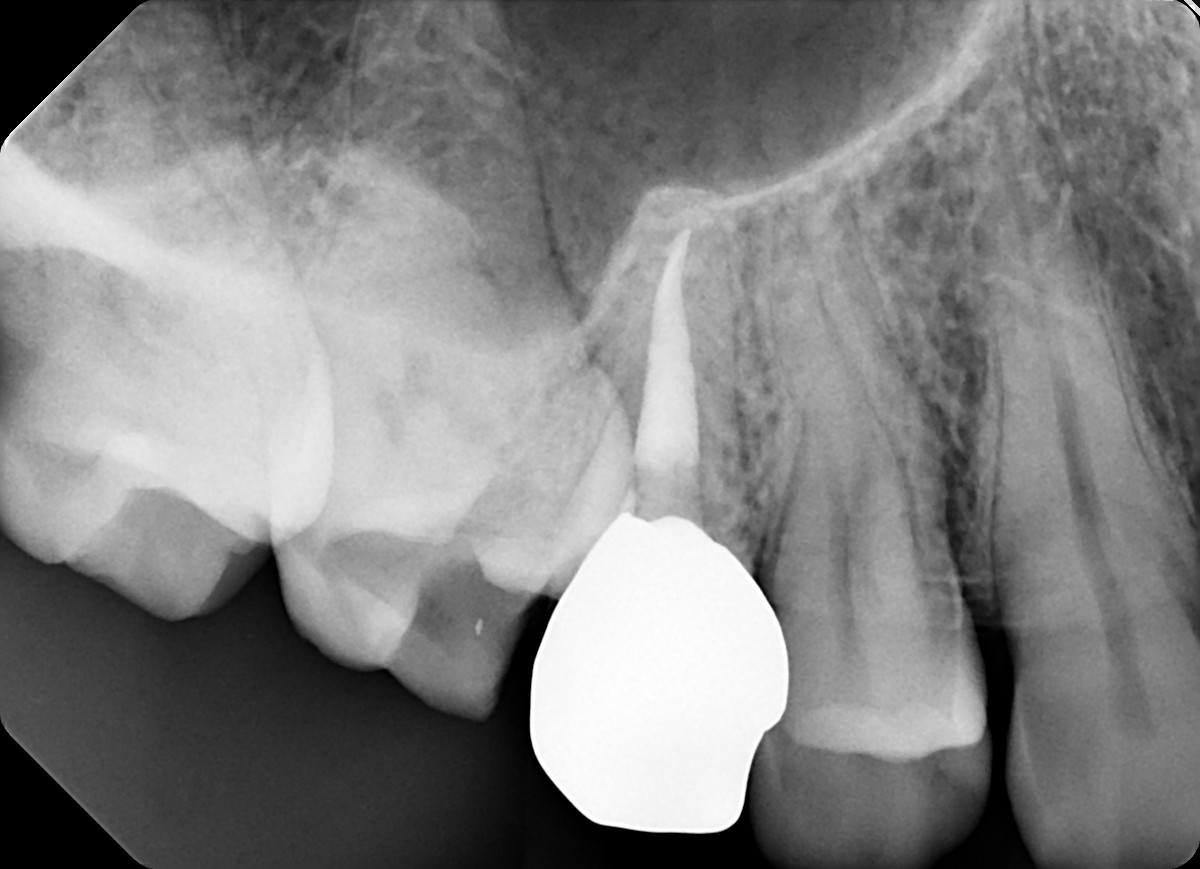

1. What option can explain the crown of the tooth # 1.4?